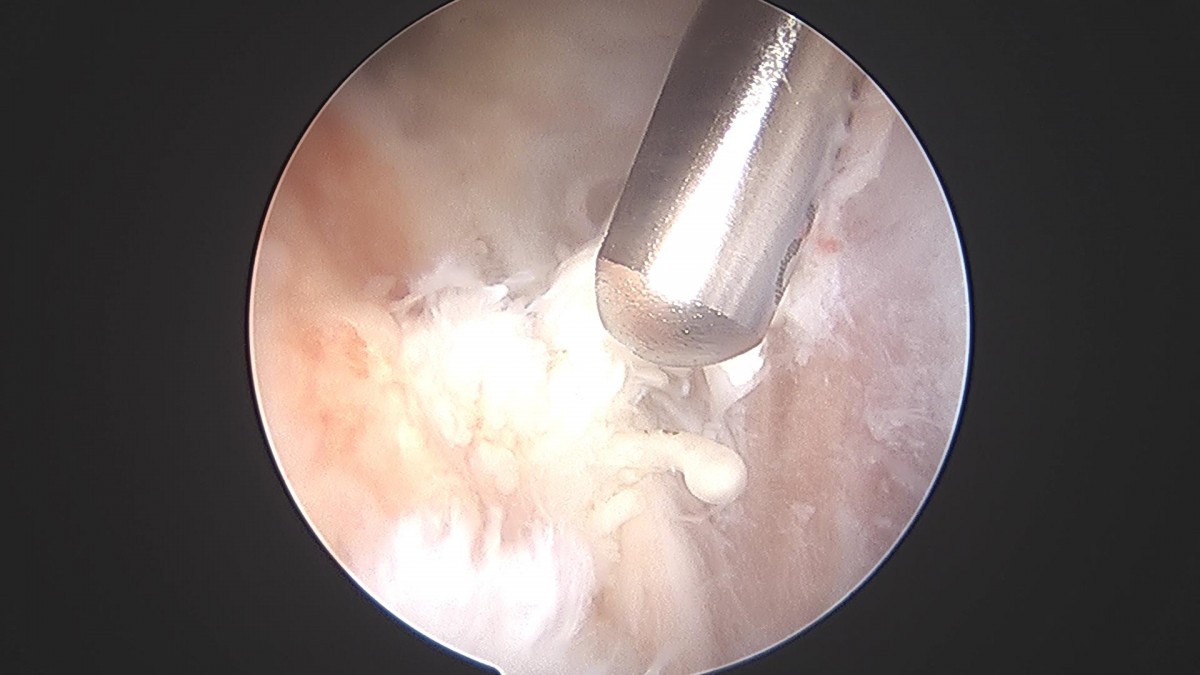

이재상원장님 어깨 견봉하감압술 및 이두박건절제술 류창O 환자